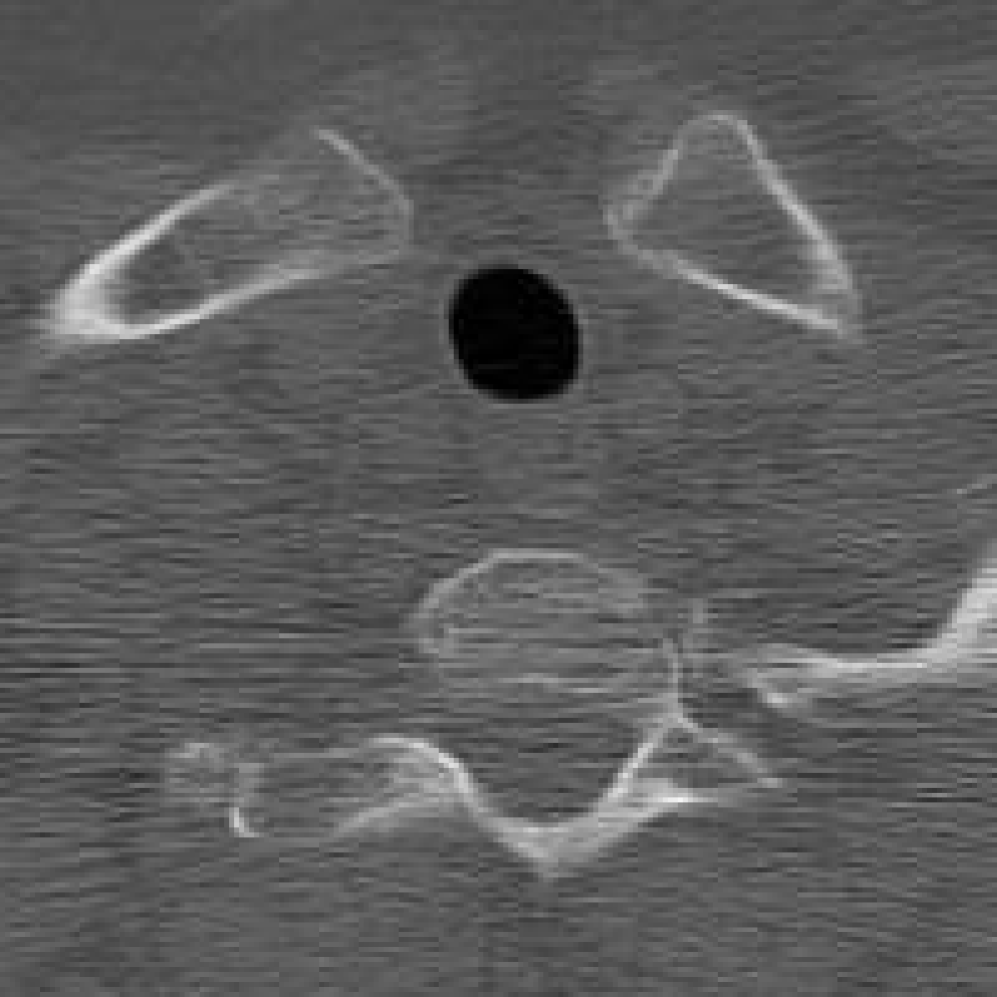

Figure 10: The visual comparison of different compression methods on a CT Heart Segmentation image.

Refer to caption

Figure 11: Zoomed-in view of the highlighted region in Figure 10.

IV-B3 Visual Comparison

Figures 7 and 8 present representative examples from the CIL dataset and their zoomed-in regions, respectively. For the CT Heart Segmentation dataset, Figures 10 and 12 illustrate typical reconstruction results, while Figures 11 and 13 further enlarge local regions to compare structural details. Across both datasets, COLI preserves fine structures and global continuity well even at relatively low bpp. Specifically, on the CIL dataset, COLI attains the lowest bitrate among INR-based methods while still maintaining clear texture details. On the CT Heart dataset, COLI also operates at a low bpp within the INR family and delivers superior visual quality with improved detail fidelity and smoother structural presentation. The zoomed-in regions show fewer blocking artifacts and smoother transitions, making COLI especially suitable for large images and medical images. These visual results validate that INR-based compression can achieve efficient storage with reliable perceptual consistency, offering practical advantages for real-world large-scale image processing.